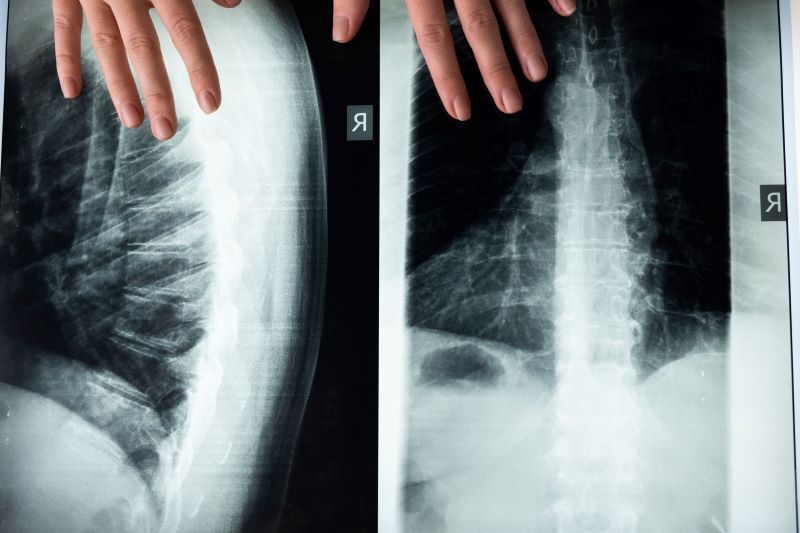

Scoliosis of the Spine

Another common spine condition is scoliosis, which is a curvature of the spine. Scoliosis can be present at birth or may develop later in life. Treatment for scoliosis may include bracing or surgery in some cases.